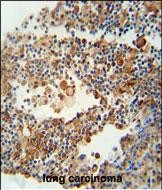

分类: 科研抗体货号: P30872别名: EF-hand domain-containing family member B, EFHB应用: WB,IHC,FCM反应种属: Human